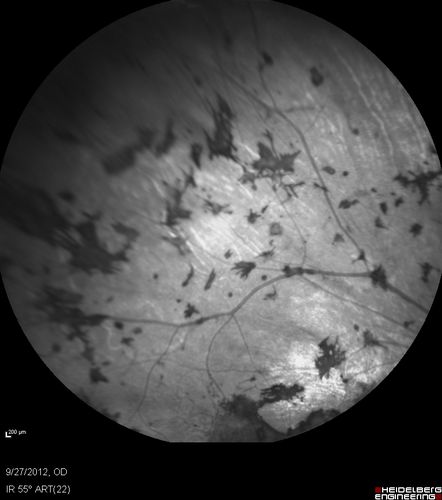

Retinitis Pigmentosa - Autosomal Dominant - Vision Loss at Young Age - Infrared

54-year-old woman has autosomal dominant retinitis pigmentosa.  Her mother and grandmother both had it and she has one son who has it and one daughter who doesn’t.  She also has a sister with it.  She lost vision since she was younger.  She had cataract surgery done in January and February of this year.  She has been seeing unusual flashing lights throughout the periphery and central vision for about the last year or two.

VISUAL ACUITY:  OD 20/160,  OS 20/160